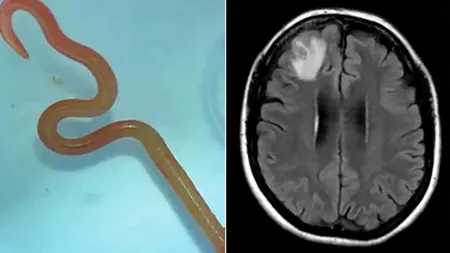

Apa care ne poate DISTRUGE creierul. „Otrava” de la robinet care omoară până la 99% dintre oamenii infectați

31 mart. 2024, 17:13